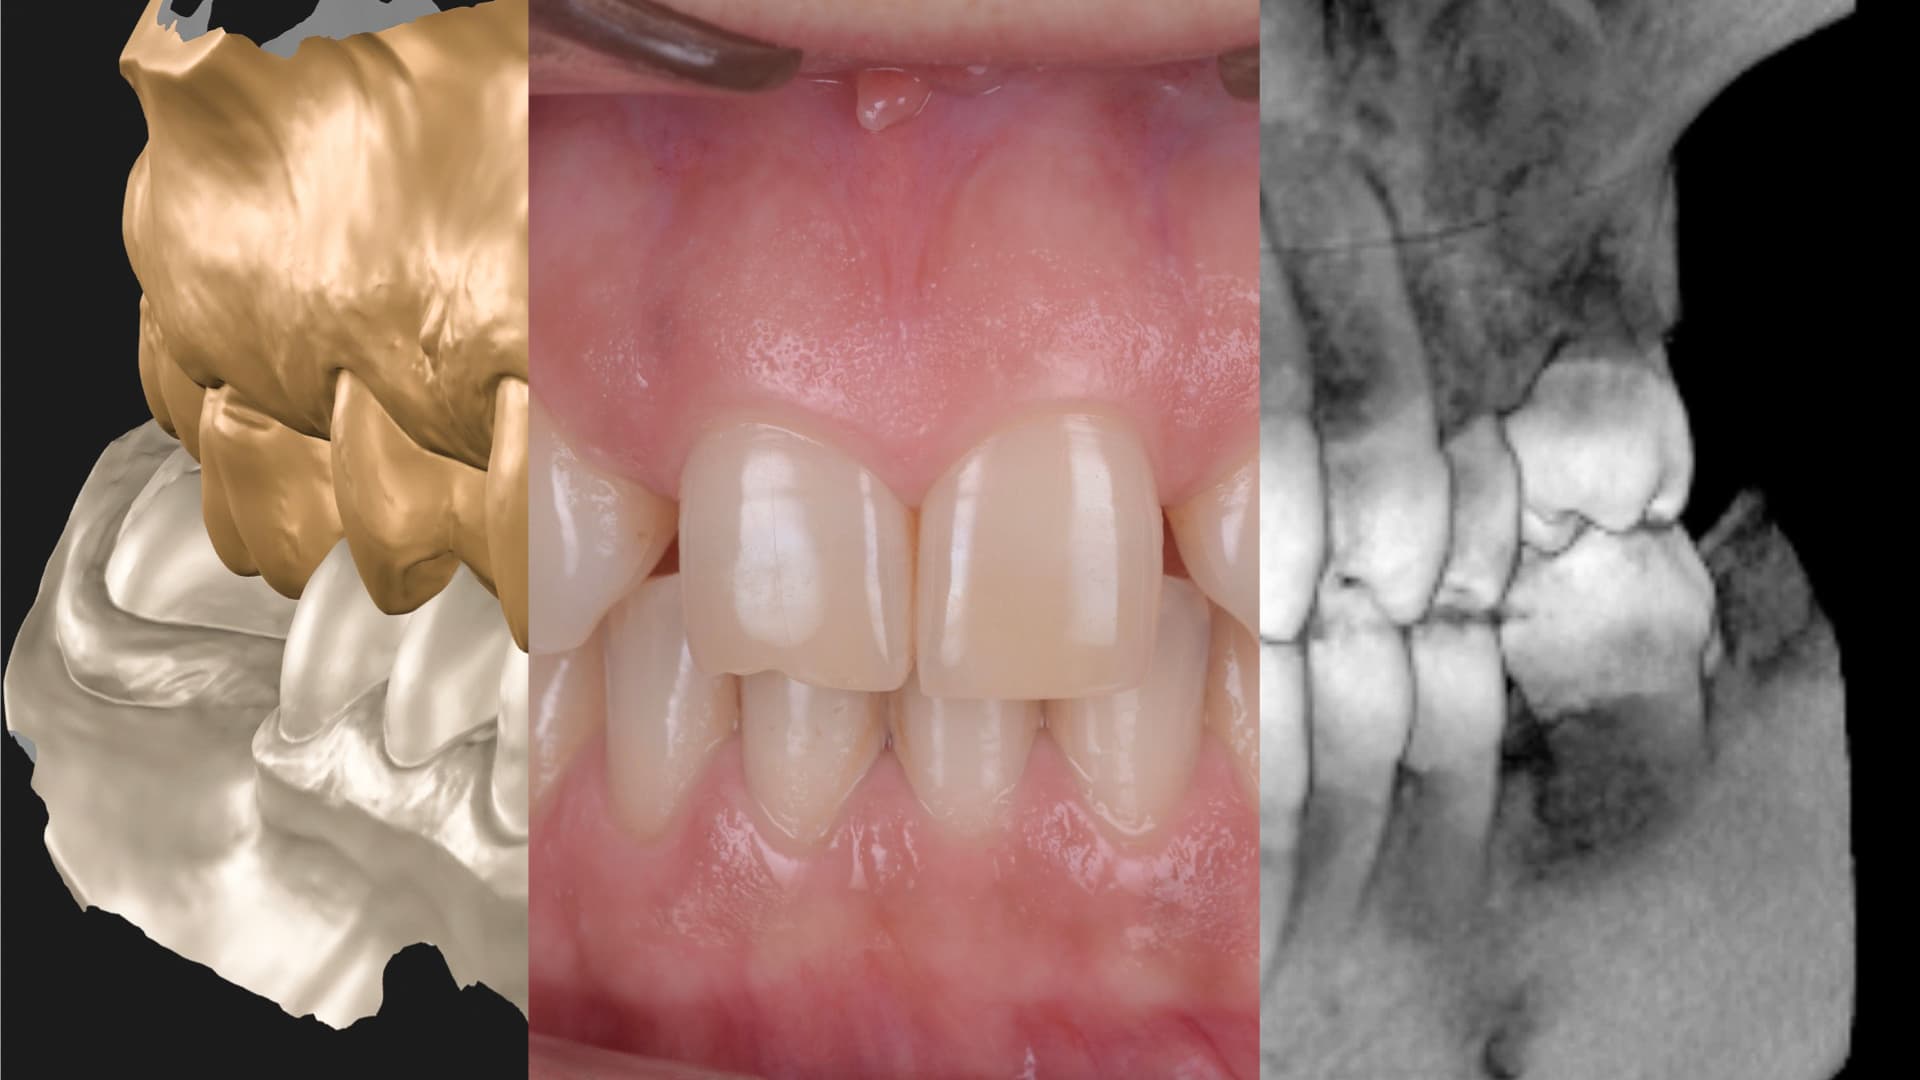

Începem cu o evaluare clinică și radiologică, folosind scanări 3D și sonde digitale pentru a măsura adâncimea pungilor parodontale, pierderea osoasă și inflamația gingivală. Acest proces ne permite să clasificăm severitatea bolii și să monitorizăm evoluția cu precizie. Cel mai important, analizăm modul în care boala parodontală influențează planul general de tratament.

Folosim CBCT, scanări intraorale și fotografii de diagnostic pentru a urmări în timp schimbările tisulare. Acest lucru ne permite să intervenim devreme, să planificăm restaurările în siguranță și să evităm supratratamentul. Echipa noastră cu experiență aliniază eforturile chirurgicale, de igienizare și protetice pentru rezultate durabile.